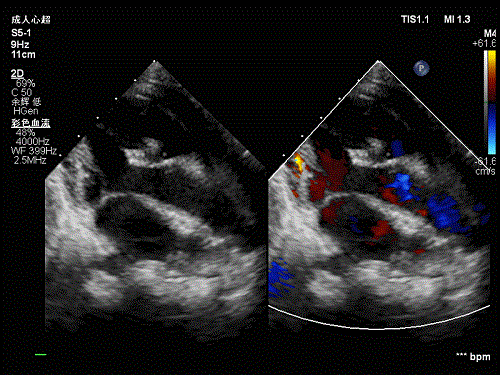

但近年來(lái),由國(guó)家心血管病中心+中國(guó)醫(yī)學(xué)科學(xué)院阜外醫(yī)院所原創(chuàng)的非放射線引導(dǎo)介入技術(shù),讓可吸收封堵器再次成為了研發(fā)熱點(diǎn)。這種非放射線引導(dǎo)介入技術(shù)采用超聲引導(dǎo)介入治療,可在人體內(nèi)清晰顯示可吸收材料,無(wú)需金屬標(biāo)記物,解決了可吸收封堵器研發(fā)的“關(guān)鍵痛點(diǎn)”。